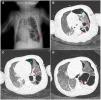

(A) Chest radiograph (anteroposterior decubitus ): multiple gas-filled cavitary lesions in LLL in the same location as the sonographic lesions compatible with pneumatocele (red arrows). (B–D) Chest CT scan with contrast. Lung window: multiple cystic lesions involving nearly the entire left lower lobe of diameters of up to 5 cm compatible with postinfectious cavitation (red arrows). Intact left upper lobe. Left pneumothorax with drainage tube (green × signs).